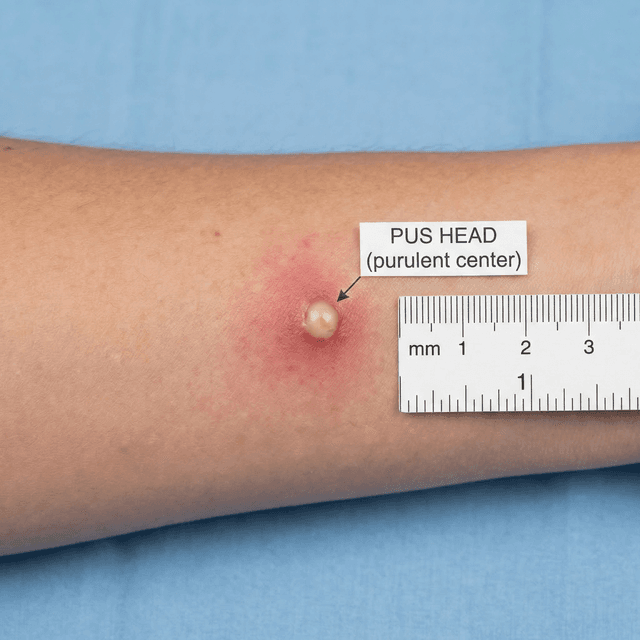

Inflammatory Acne: Papules, Pustules, and Why Your Skin Hurts

Inflammatory acne is the red, painful kind that actually hurts. Understanding the immune response behind it changes how you treat it and helps you stop making it worse.

Whiteheads (Closed Comedones): What They Are, Why They Form, and How to Get Rid of Them

Those small, flesh-colored bumps that won't pop? They're closed comedones — and they require a completely different approach than regular pimples. Here's what dermatologists recommend.

Blackheads (Open Comedones): Why They're Dark, How to Remove Them Safely, and What Actually Prevents Them

Blackheads aren't caused by dirt — they're oxidized oil plugs in open pores. Here's the science behind why they form and the dermatologist-approved ways to actually get rid of them.

Papules: Understanding Small Red Acne Bumps and How to Treat Them

Those small, red, tender bumps without a visible head? They're papules — a sign your acne has become inflammatory. Here's what's happening beneath the surface and what to do about it.

Pustules: The Classic Pimple — What's Inside, Should You Pop It, and How to Treat It

Pustules are what most people picture when they think 'pimple' — red bumps with a white or yellow center. Here's what's actually inside them, whether popping is ever okay, and what dermatologists recommend.